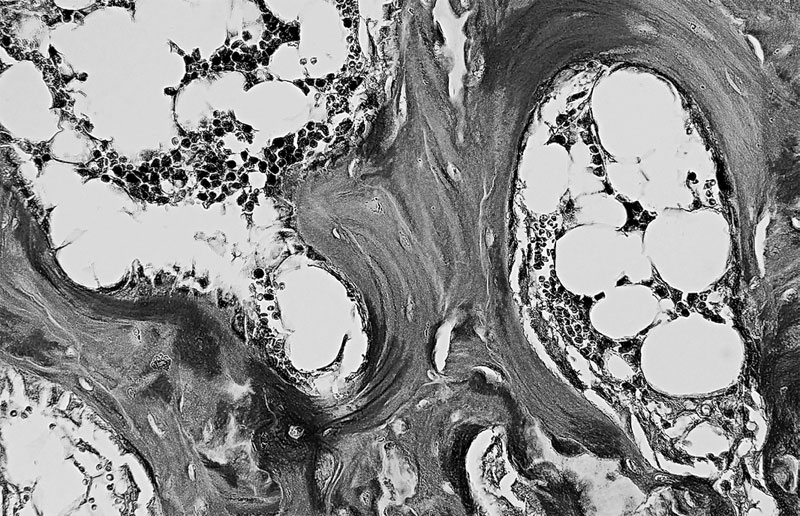

Особенность третья – костная ткань имеет пластинчатое строение. Каждая пластинка представляет собой тонкий пучок параллельно расположенных коллагеновых волокон, между которыми находятся остеоциты и аморфное вещество, содержащее кристаллы минеральных солей. Волокна соседних пластинок располагаются под углом друг к другу, часть их переходит из одной пластинки в другую, что обуславливает их плотное соединение, а, следовательно, и высокую прочность костей. Пластинок, располагаются вокруг каналов, в которых проходят кровеносные сосуды и нервы, образуя многослойные концентрические цилиндры.

Костные пластинки, образующие канал для кровеносного сосуда (в центре)